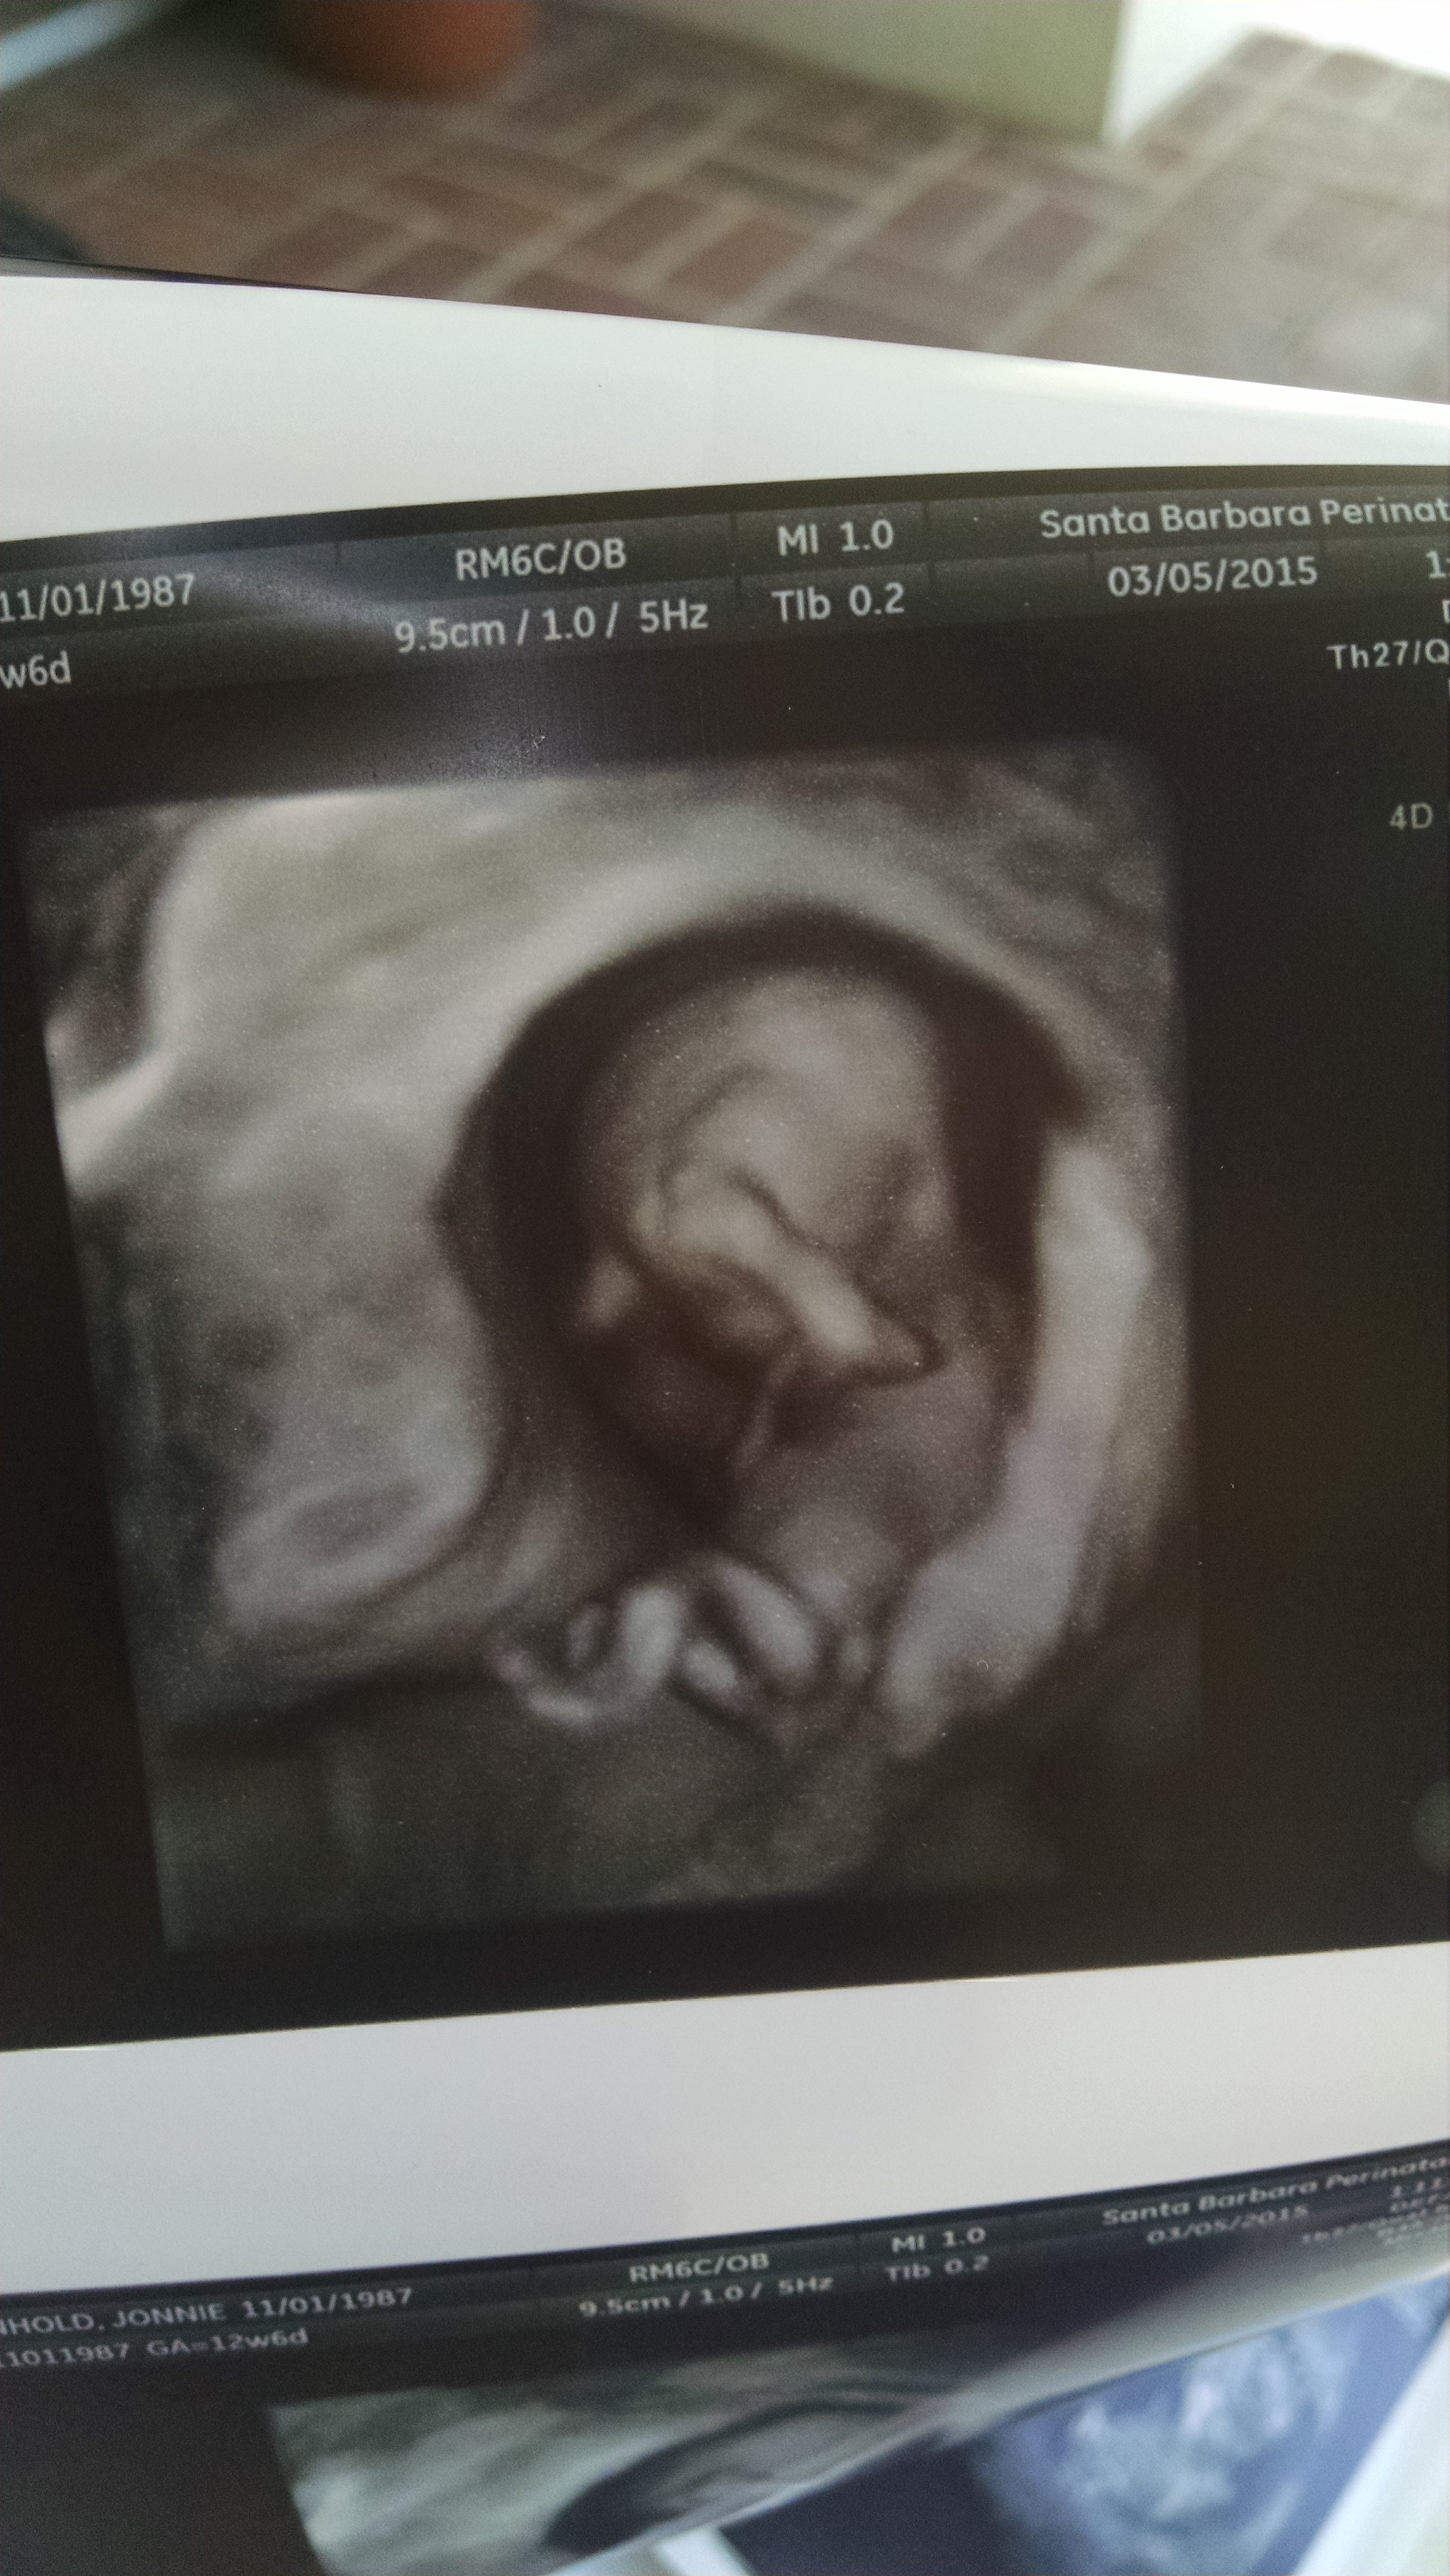

Second picture is 8 weeks 1 day also transvaginal